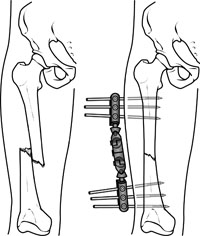

In this type of operation, metal pins or screws are placed into the broken bone above and below the fracture site. The pins or screws are connected to a metal bar outside the skin. This device is a stabilizing frame that holds the bones in the proper position while they heal.

In cases where the skin and other soft tissues around the fracture are badly damaged, an external fixator may be applied until surgery can be tolerated.During this operation, the bone fragments are first repositioned (reduced) in their normal alignment, and then held together with special screws or by attaching metal plates to the outer surface of the bone. The fragments may also be held together by inserting rods down through the marrow space in the center of the bone.

An external fixator applied to a broken thighbone.